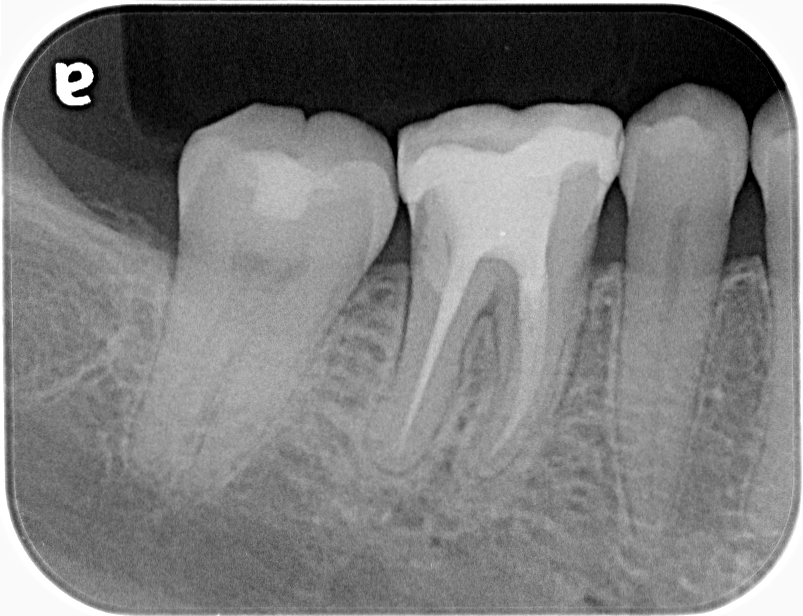

術前の診査では根分岐部に5mm前後のポケットと、透過像を認めます。

顕微鏡での診査では破折線は分岐部と一致しない部位に限局的に存在したため、保存可能な可能性が高いと判断し根管治療を開始しました。

術後半年経過を見ましたが、分岐部のポケットと透過像が改善なく排膿を認めたため、歯内歯周疾患と診断し再生療法を行いました。